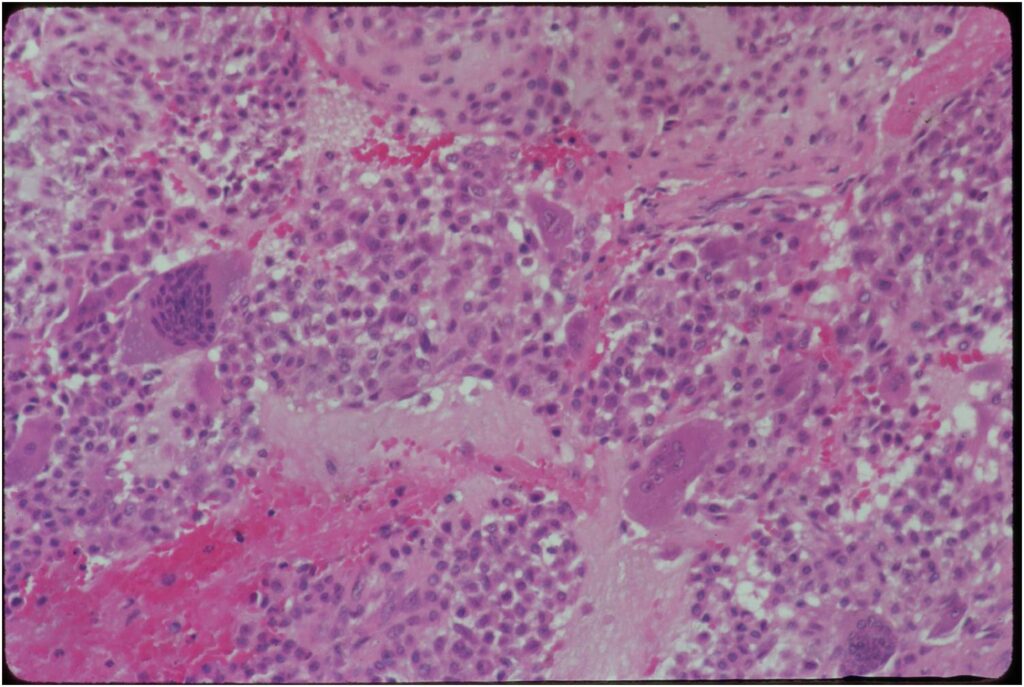

Gross Pathology

- Grossly variable appearance

- Grey/yellow/brown and gritty if has interspersed calcifications

- Interspersed red areas from hemorrhagic necrosis

- May be blue-grey areas from the chondroid matrix

- Rim of sclerotic bone is visible in totally resected specimens

- Lesion may be fully cystic with solid foci of tumor tissue at periphery

- May undergo aneurysmal bone cyst change (ABC change)

- Variable appearance depending on percentage of cells, necrosis, cartilage matrix formation and ABC change

- ABC component 5-15% of tumors